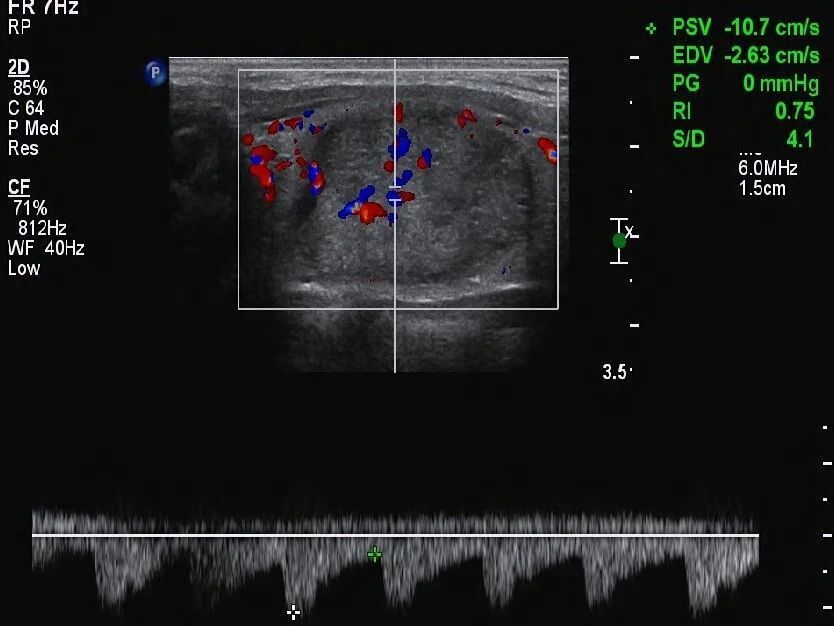

声晕特征的分析价值

声晕特征在结节周围存在着,可为诊断提供重要线索。薄且均匀的声晕存在着,肿瘤一般是良性的,代表结节生长不迅速,对周围其他组织施加正常均匀压迫形成这种情况。这种声晕,在甲状腺结肠里颇为常见。

一些结节属于恶性,它的声晕呈现特定特点,这些声晕特征并非单一统一,有的声晕完全不存在,呈现为空环状,有的厚,然而声墙的厚度不均匀,这种声晕不均匀的情况,恰恰是浸润恶性生长的趋势所造成的特性,是判断结节为良性或恶行类型的重要参考指标之一的体现,而这一点同样能够用作判断依据来加以确诊恶性。